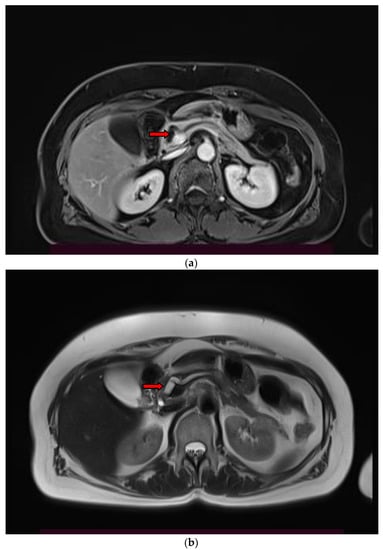

2. Imaging Findings